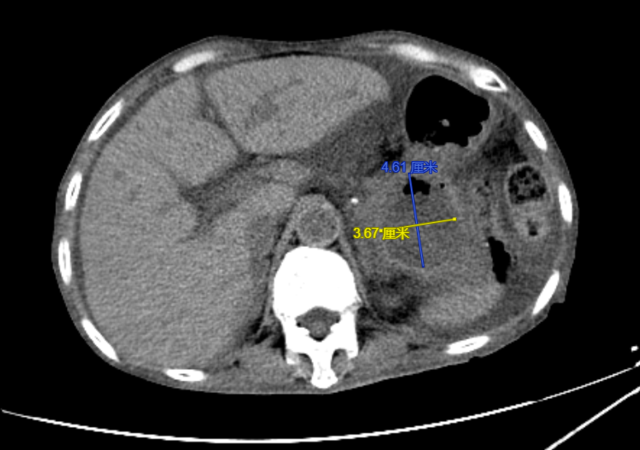

程女士,70岁,反复腹胀4天余,来到昆山市一医院消化内科就诊,通过问诊得知程女士去年7月因“急性腹痛发作”于外院确诊为急性重症胰腺炎,经治疗后,胰腺炎病情虽有好转,但不幸的是:程女士出现了胰腺炎治疗后的并发症——胰腺假性囊肿,门诊复查腹部CT提示胰尾部假性囊肿形成,大小约10*8.5cm,程女士此次腹胀、恶心呕吐考虑是由于巨大囊肿压迫所致。程女士此前已辗转于昆山及周边多家医院就诊,由于程女士年龄大,病情重,大量腹水(超声腹水深度为12cm),营养差,白蛋白16.3g/L(正常值:35-50g/L),行进一步手术治疗风险极大,程女士和家属焦急万分。

手术前

术后程女士腹痛、腹胀症状迅速得到了缓解,复查CT示囊肿较前显著缩小,目前已康复出院。